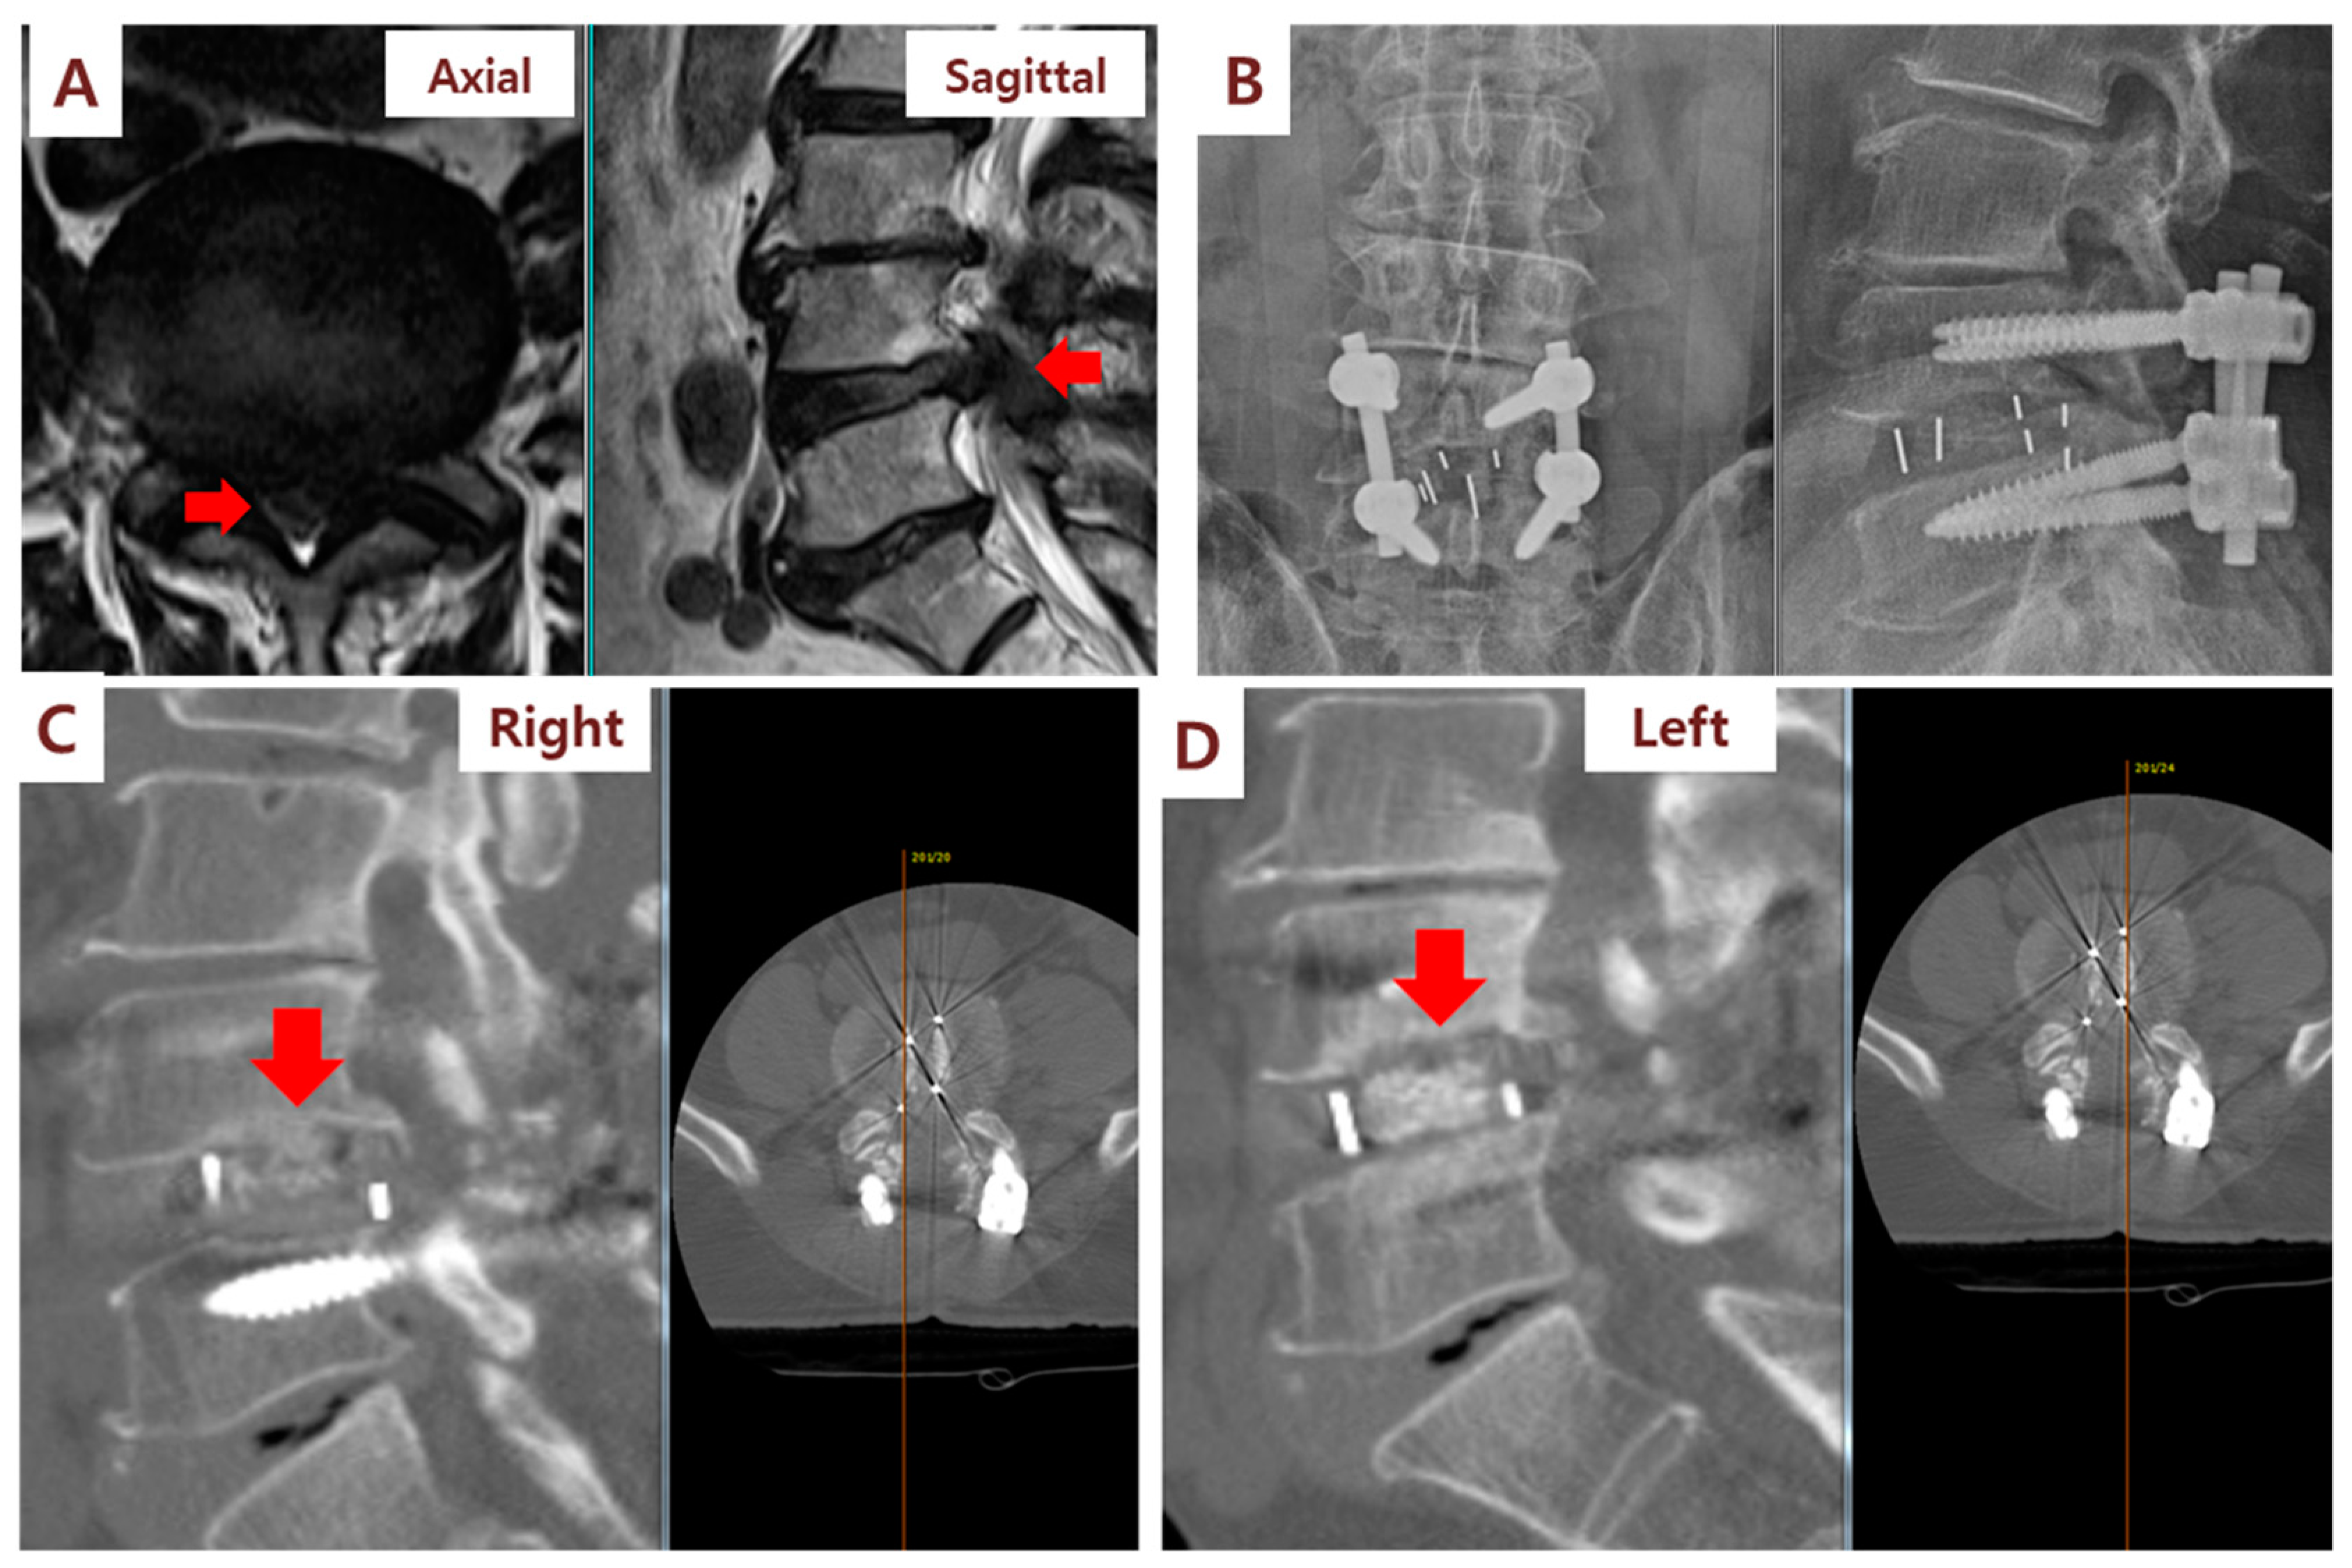

3.2. Clinical and Radiographic Outcomes